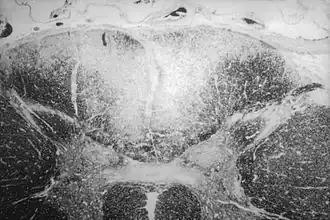

Гистопатологические изменения, вызываемые T. pallidum, окраска серебрением